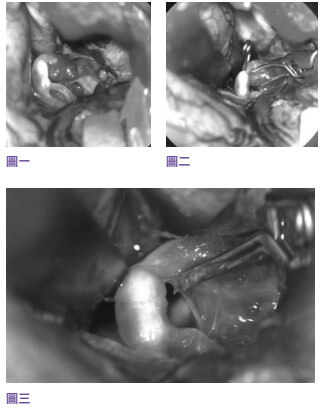

Mr. Ho took the advice of his doctor to undergo minimally invasive cerebrovascular surgery to prevent stroke. Since aneurysms are located in the position of the middle artery branch, normal minimally invasive intravascular stent therapy surgery might have the risk lead to the embolism of blood vessels, so the author recommended that Mr. Ho do craniofacial surgery, that is, microscopic minimally invasive cerebrovascular surgery aneurysm clamping surgery. During the three- to four-hour operation, the neurosurgeon carefully separated the nerves and cerebrovascular vessels under a microscope, then used titanium clips to clamp the aneurysm located in the middle artery branch, and the timing bomb in Mr. Ho’s brain was removed, changing the fate of future hemorrhagic strokes (see figures I, II, III). The day after the operation, Mr. Ho went home to rest and continued to receive conservative treatment for sciatic nerve pain for half a year.